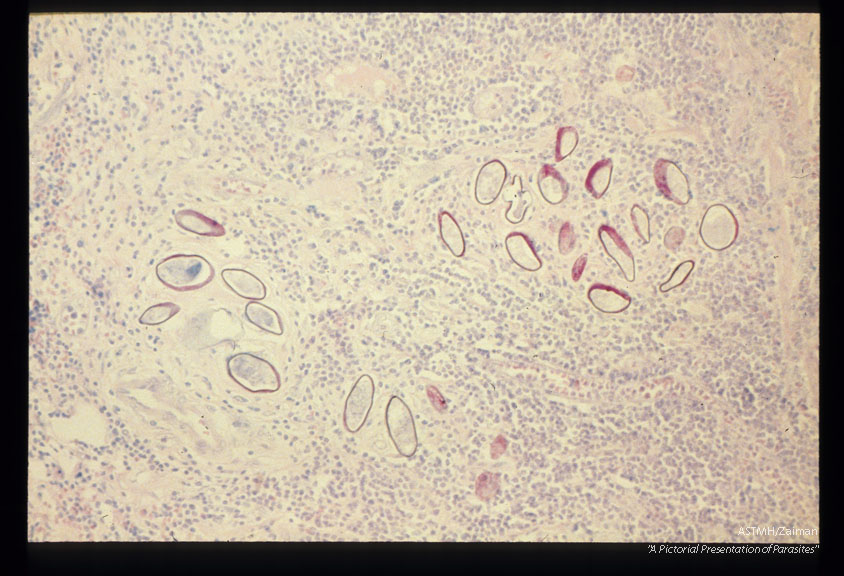

Multiple sections through appendix. Note that the eggs are acid fast.

Schistosoma japonicum

Description: Multiple sections through appendix. Note that the eggs are acid fast.